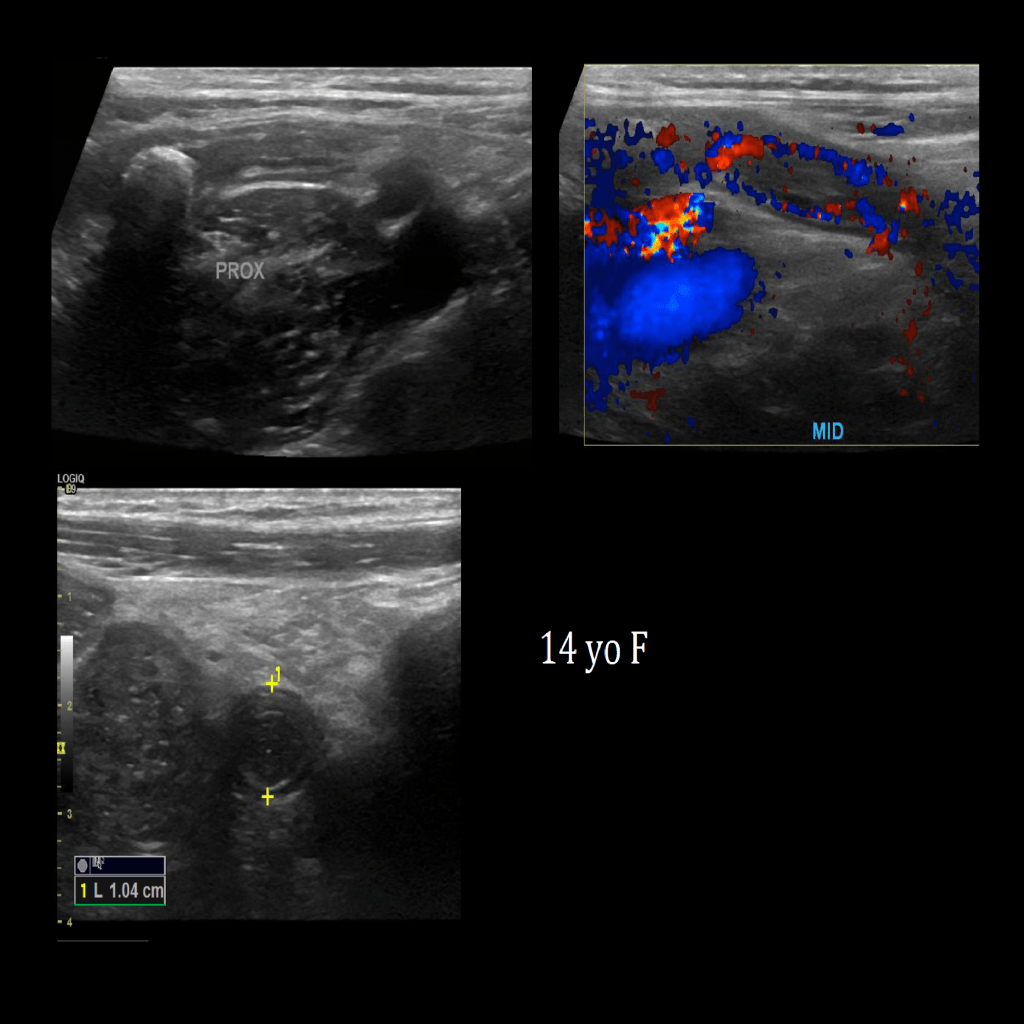

Appendicitis 13

Acute appendicitis @ 1 cm with L2-9mhz and L6-24mhz transducer GE Logiq e10.